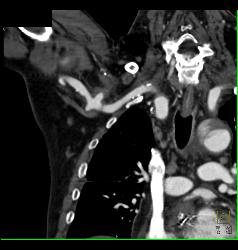

Trauma to Right Axillary Artery With Pseudoaneurysm